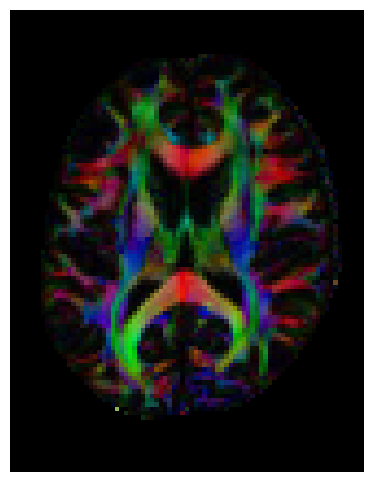

We can also find the peak directions (maxima) of the ODFs with peaks_from_model.

# Find peak directions (maxima) of the ODFs

peaks_csd = peaks_from_model(model=csd_model,

data=data,

sphere=default_sphere,

relative_peak_threshold=0.5,

min_separation_angle=25,

mask=white_matter,

return_sh=True,

parallel=False)

print("CSD peaks computed. SH shape:", peaks_csd.shm_coeff.shape)

CSD peaks computed. SH shape: (81, 106, 76, 45)

scene = window.Scene()

scene.add(

actor.peak_slicer(

peaks_csd.peak_dirs[20:50, 55:85, 38:39], peaks_values=peaks_csd.peak_values[20:50, 55:85, 38:39],

colors=None,

)

window.record(scene=scene, out_path="csd_direction_field.png", size=(600, 600))

Image("csd_direction_field.png")

../_images/e0431602bb8df52f997a45c7b57ac89b59c64a0c4d37c0bfbe360dd212068884.png